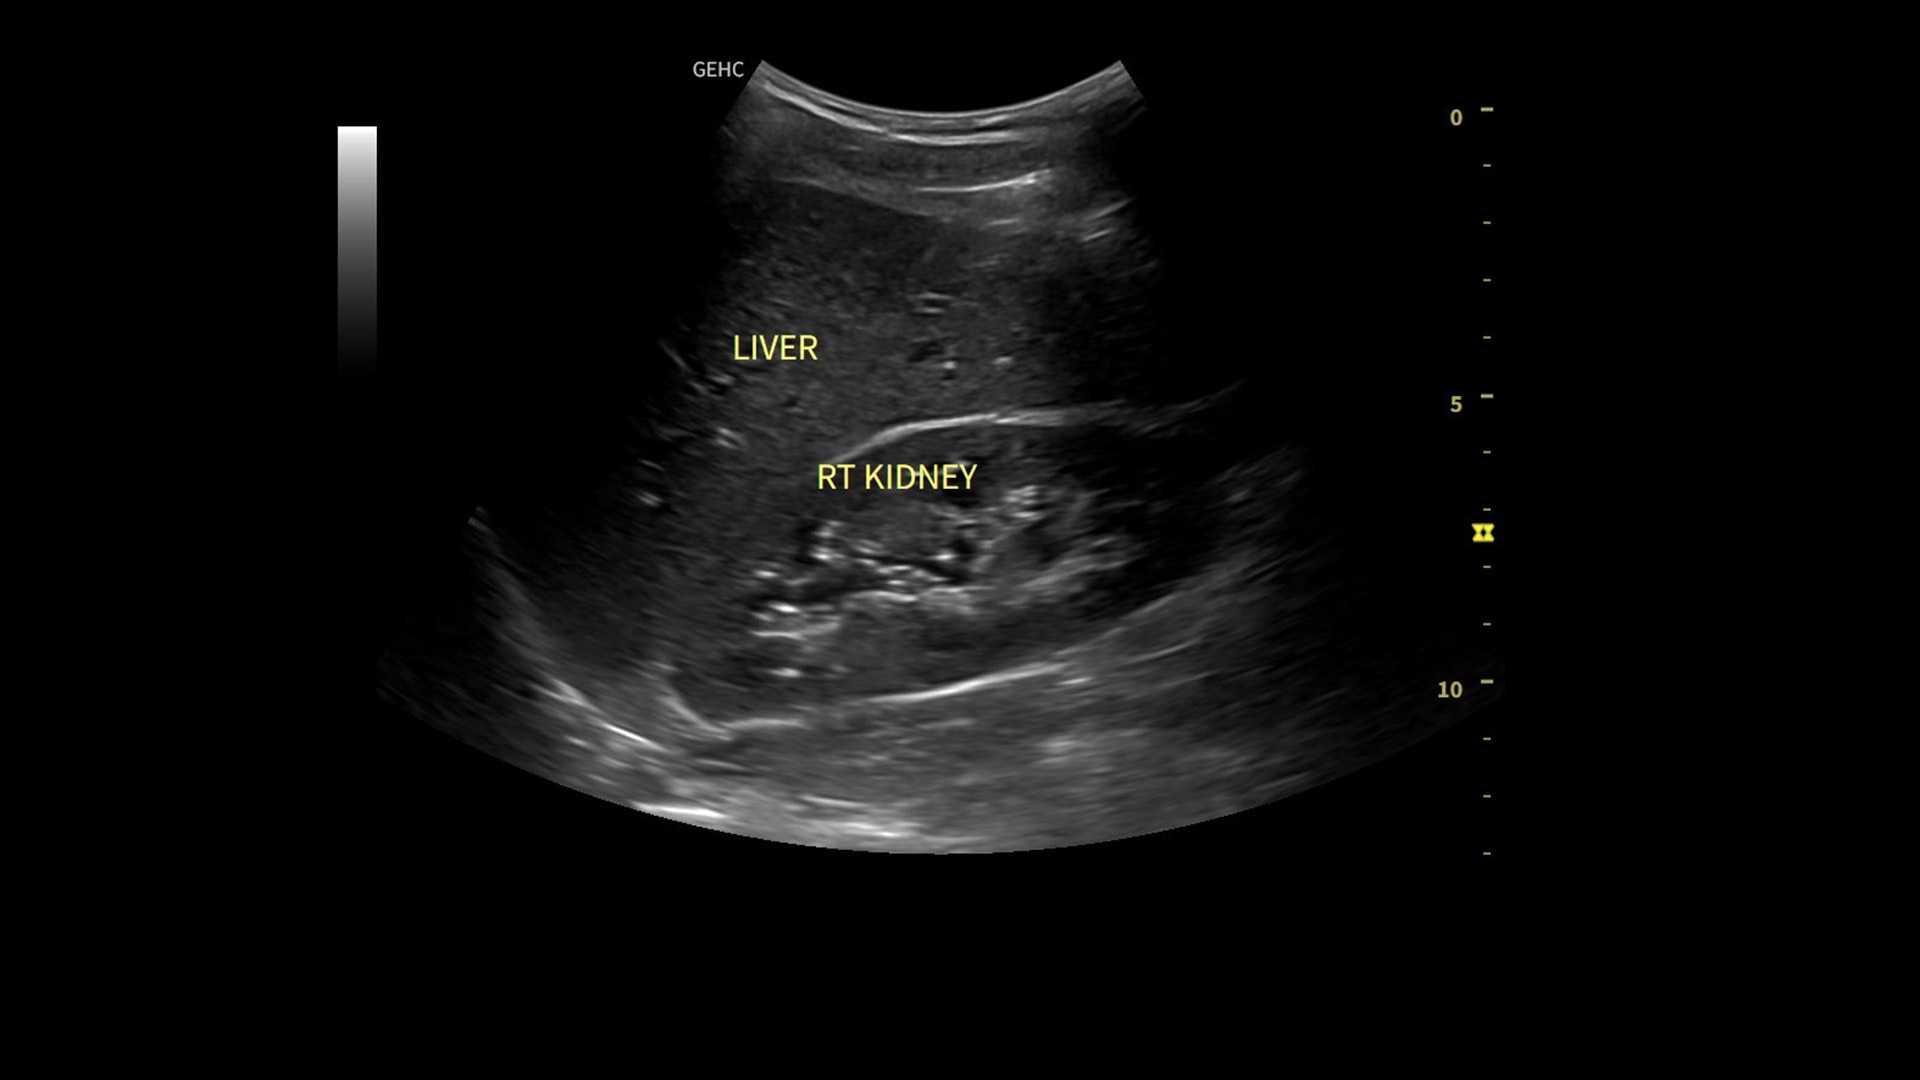

• Use automated labeling in the RUQ with Whizz Label

AI-enabled labeling of the right kidney, gallbladder and liver